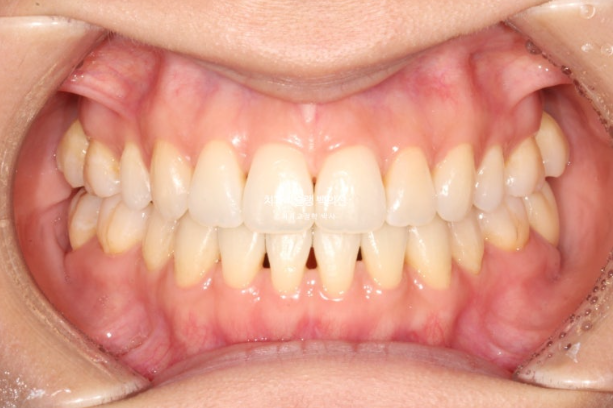

3월부터 5월까지 2달간 7개 장치를 모두 낀 후 모습입니다.

25.05

윗니는 제자리로 잘 들어갔으나 아래 앞니 블랙트라이앵글이 여전히 큽니다.

앞니 배열 완료입니다.

아래 앞니 블랙트라이앵글을 더 없애고자 추가장치 제작에 들어갑니다.